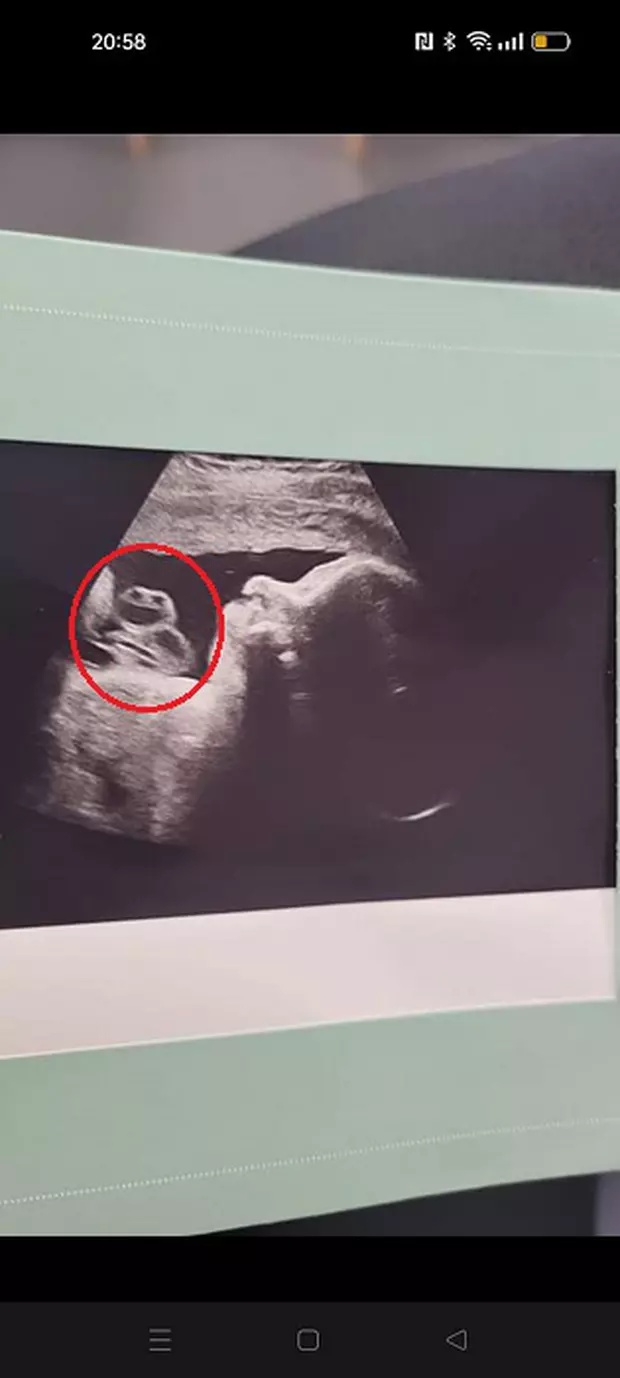

Angharad Murray este coafeză în Țara Galilor și a observat în imaginea de la ecografie că, pe lângă trupul fătului, se mai vedea o siluetă deasupra burticii copilului, ceva straniu ce părea a avea doi ochi și un zâmbet larg.

În realitate, ceea ce femeia a văzut și internauții au asociat cu imaginea broscoiului Kermit din Muppet Show, nu este altceva decât cordonul ombilical al copilului.

Unii internauți au spus că este vorba despre una dintre Țestoasele Ninja, dar cei mai mulți au fost ferm convinși că ceea ce e în imagine seamănă izbitor cu broscoiul din Muppet Show.

„Mi-am făcut mai multe ecografii, din cauza vârstei mele și aceasta a fost a doua. Mi-au spus că totul este în regulă și apoi mi-au dat poza. De fapt, nu m-am uitat la ea până nu am așteptat să văd ce spune doctorul. Primul meu gând a fost că arată ca acolo este ceva care seamănă cu o broască.

Ca broscoiul Kermit. Nu mă pot opri să mă uit la poză, mă face să râd. De asemenea, este plăcut să văd printre internauți și oameni care lucrează în spitale și spun că de fapt este vorba despre cordonul ombilical' – a declarat femeia, citată de Mirror.